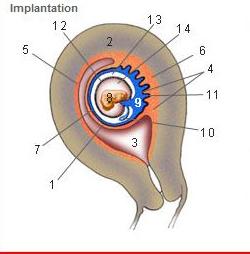

Where is the Desidua Capsularis?

1

Where is the Desidua basalis?

6

Where is the Desidua parietalis?

5

Where is the chorion frondosum?

11

Where is the amnion?

12

Where is the chorionic cavity?

13